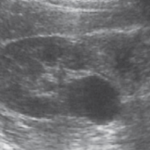

4-Extrarenal pelvis

هنا ببساطة يتواجد حوض الكلية خارج الكلية وكأنه كيس خارجي. الأهمية هنا تكمن في تمييزه بأنه تغير طبيعي وليس توسع في حوض الكلية أو كيس. التفرقة بينه وبين hydronephrosis تكون في عدم وحود توسع في calycis كما هو الحال في hydronephrosis.

في هذه الحالات يفضل التصوير بشكل transverse للتأكد.

5-Fetal lobulations

في مرحلة تطور الجنين تتكون الكلية عن طريق تلاحم عدة فصوص lobes. وهذه الفصوص قد تستمر إلى مابعد مرحلة البلوغ. تظهر بشكل تموجات في القشرة الخارجية للكلية. من المهم أن لا نخطئ في تشخصيها كندبة scar أو ورم في الكلية.